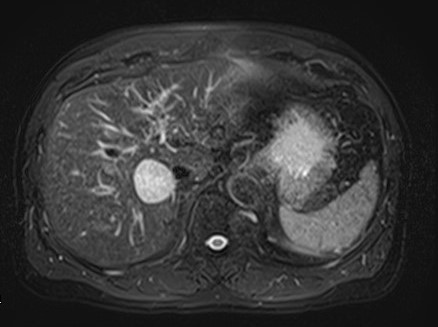

她這一年常覺得喘、右上腹隱隱脹脹,體重也掉了幾公斤。腹部超音波發現:

膽囊多發性結石

總膽管明顯擴張(約2.5公分)

醫師懷疑不只是結石那麼單純,轉至本中心做MRCP(磁振膽胰管攝影)。

影像顯示:整個總膽管呈現紡錘狀擴張,符合「先天性總膽管囊腫」(成人型,Type I)。這種情況在成人很少見,100個人裡大概只有10-20個會出現症狀,常見的是腹痛、黃疸,或反覆膽管發炎。更重要的是,這類囊腫長久下來,發生膽管癌的機率比一般人高10-20倍。林女士目前沒有急性發炎,目前先用藥物控制症狀,每6個月回來做一次核磁共振追蹤,暫時不需要開刀。她說:「現在知道是什麼問題,內心平靜多了。」